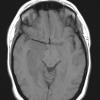

NEOPLASMS (GLIAL)

Astrocytoma, IDH-mutant, WHO Grade 2 (2)